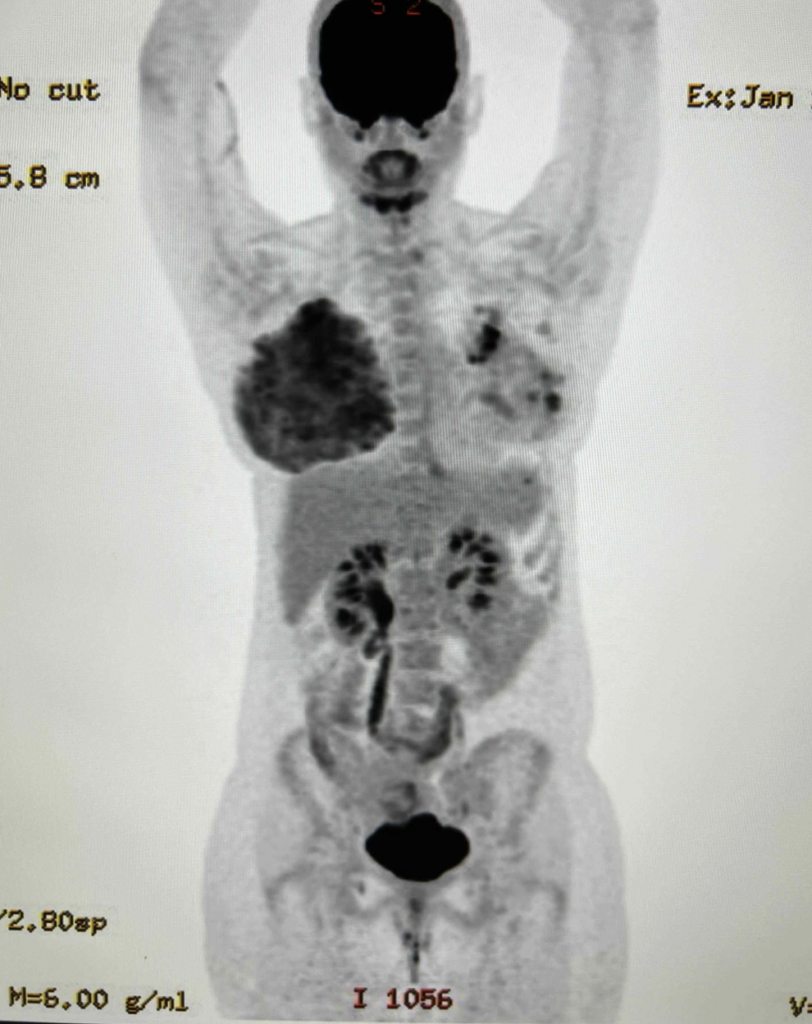

Staging PET CT showing a right breast tumor, right lymph node involved with cancer, and a left breast area of “avidity” during lactation. This left breast area was biopsied and showed lactational changes only.

metabolic activity of the breast during lactation

This PET scan performed above for a left breast cancer (shown by the black areas in the left breast) demonstrates the remarkable metabolic activity of the lactating breast (right).  This patient was mainly feeding on her right breast due to skin changes and inability to feed the infant on her left breast with cancer.  You see that the lactating breast is actually more “FDG avid” (meaning it takes up more of the radio nucleotide, FDG, that the PET scan uses to determine metabolic activity) than the breast cancer itself.